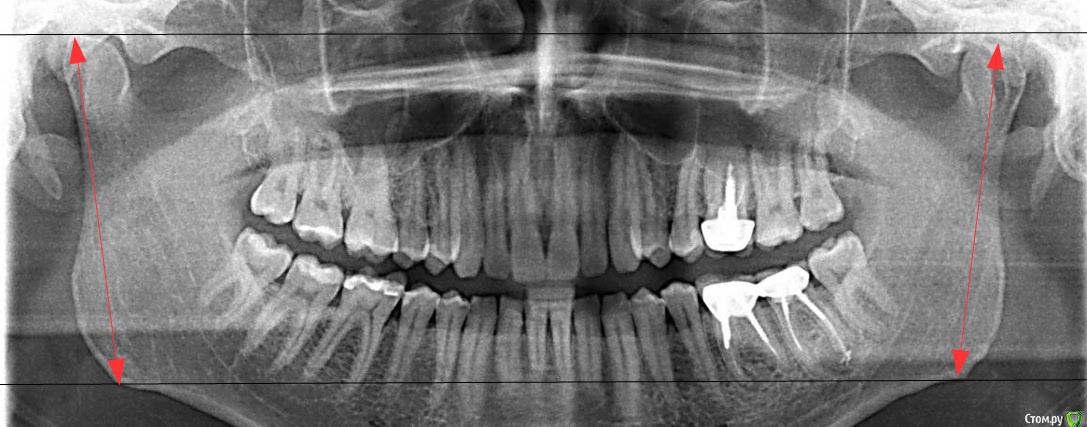

Мне 34 года. В связи с необходимостью перелечивания корней 36 и 37 зубов пришлось заменить металлокерамическую коронку. Однако, она мне не подошла: через несколько дней при смыкании нижняя челюсть начала какбы съезжать впред и влево, начали соприкасаться (ранее такого не было) передние левые зубы. Доктор объяснил это занижнием коронки в области 36 зуба. Сделали новую коронку, которую я носил неделю, но она мне тоже была неудобна (как бы завышала). Ее опять изменили, немного занизили. В результате почти месяц, ношения разных вариантов и в итоге:

ЗЫ. Снимок ВНЧС (по просьбе доктора) сделан в "неудобном" положении смыкания.

- померила линейкой ветви - разницы не нашла, тем более в 5 мм.

>>- померила линейкой ветви - разницы не нашла, тем более в 5 мм.

А если посмотреть как на вложенном ниже рисунке?

измерила по Вашим стрелочкам. разница в 1 мм (и то погрешность может быть)

Насчет разницы в длинне ветвей спорить не могу - возможно Вы правы.